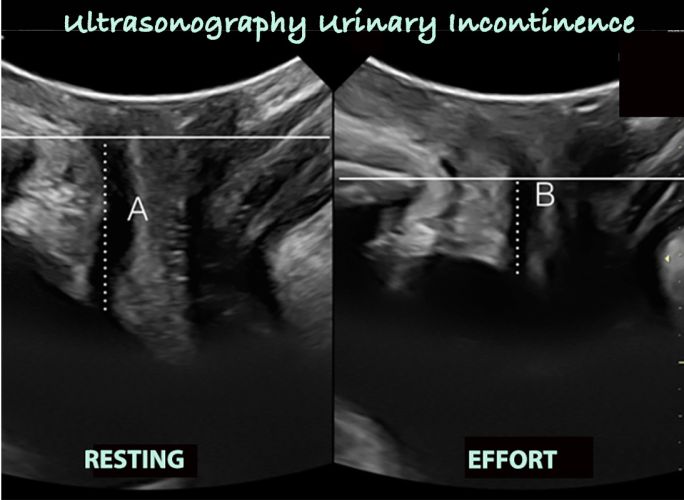

The continuous line marks the horizontal with respect to the pubic

the discontinuous line marks the mobility of the urethra, which is obtained from the difference between A and B (rest and effort)